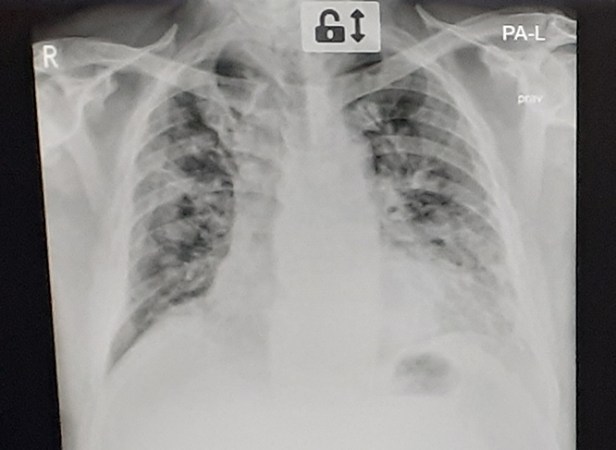

При COVID-19, за разлика от другите вирусни пневмонии, промените са изключително двустранно изразени, по-често периферно разположени. Могат да се видят в горните дялове на белия дроб, в средните, но по-често са в долните. Промените тип „матово стъкло” на образните изследвания отразяват възпалението на алвеолите.

Когато пневмонията излиза от острата фаза, много бързо се стига до сраствания. Наблюдения на лекари при хоспитализирани пациенти с COVID-19 във ВМА показват, че често при тежко болни пациенти фиброзата, която се развива, е много сериозна и на практика намаля всички белодробни обеми, като може да ги направи кислородозависими и да ги инвалидизира, дори във възраст, в която белият дроб изобщо не е остарял. Фиброзата е крайна фаза на преструктуриране на белодробната тъкан, където газообмен не се осъществява.